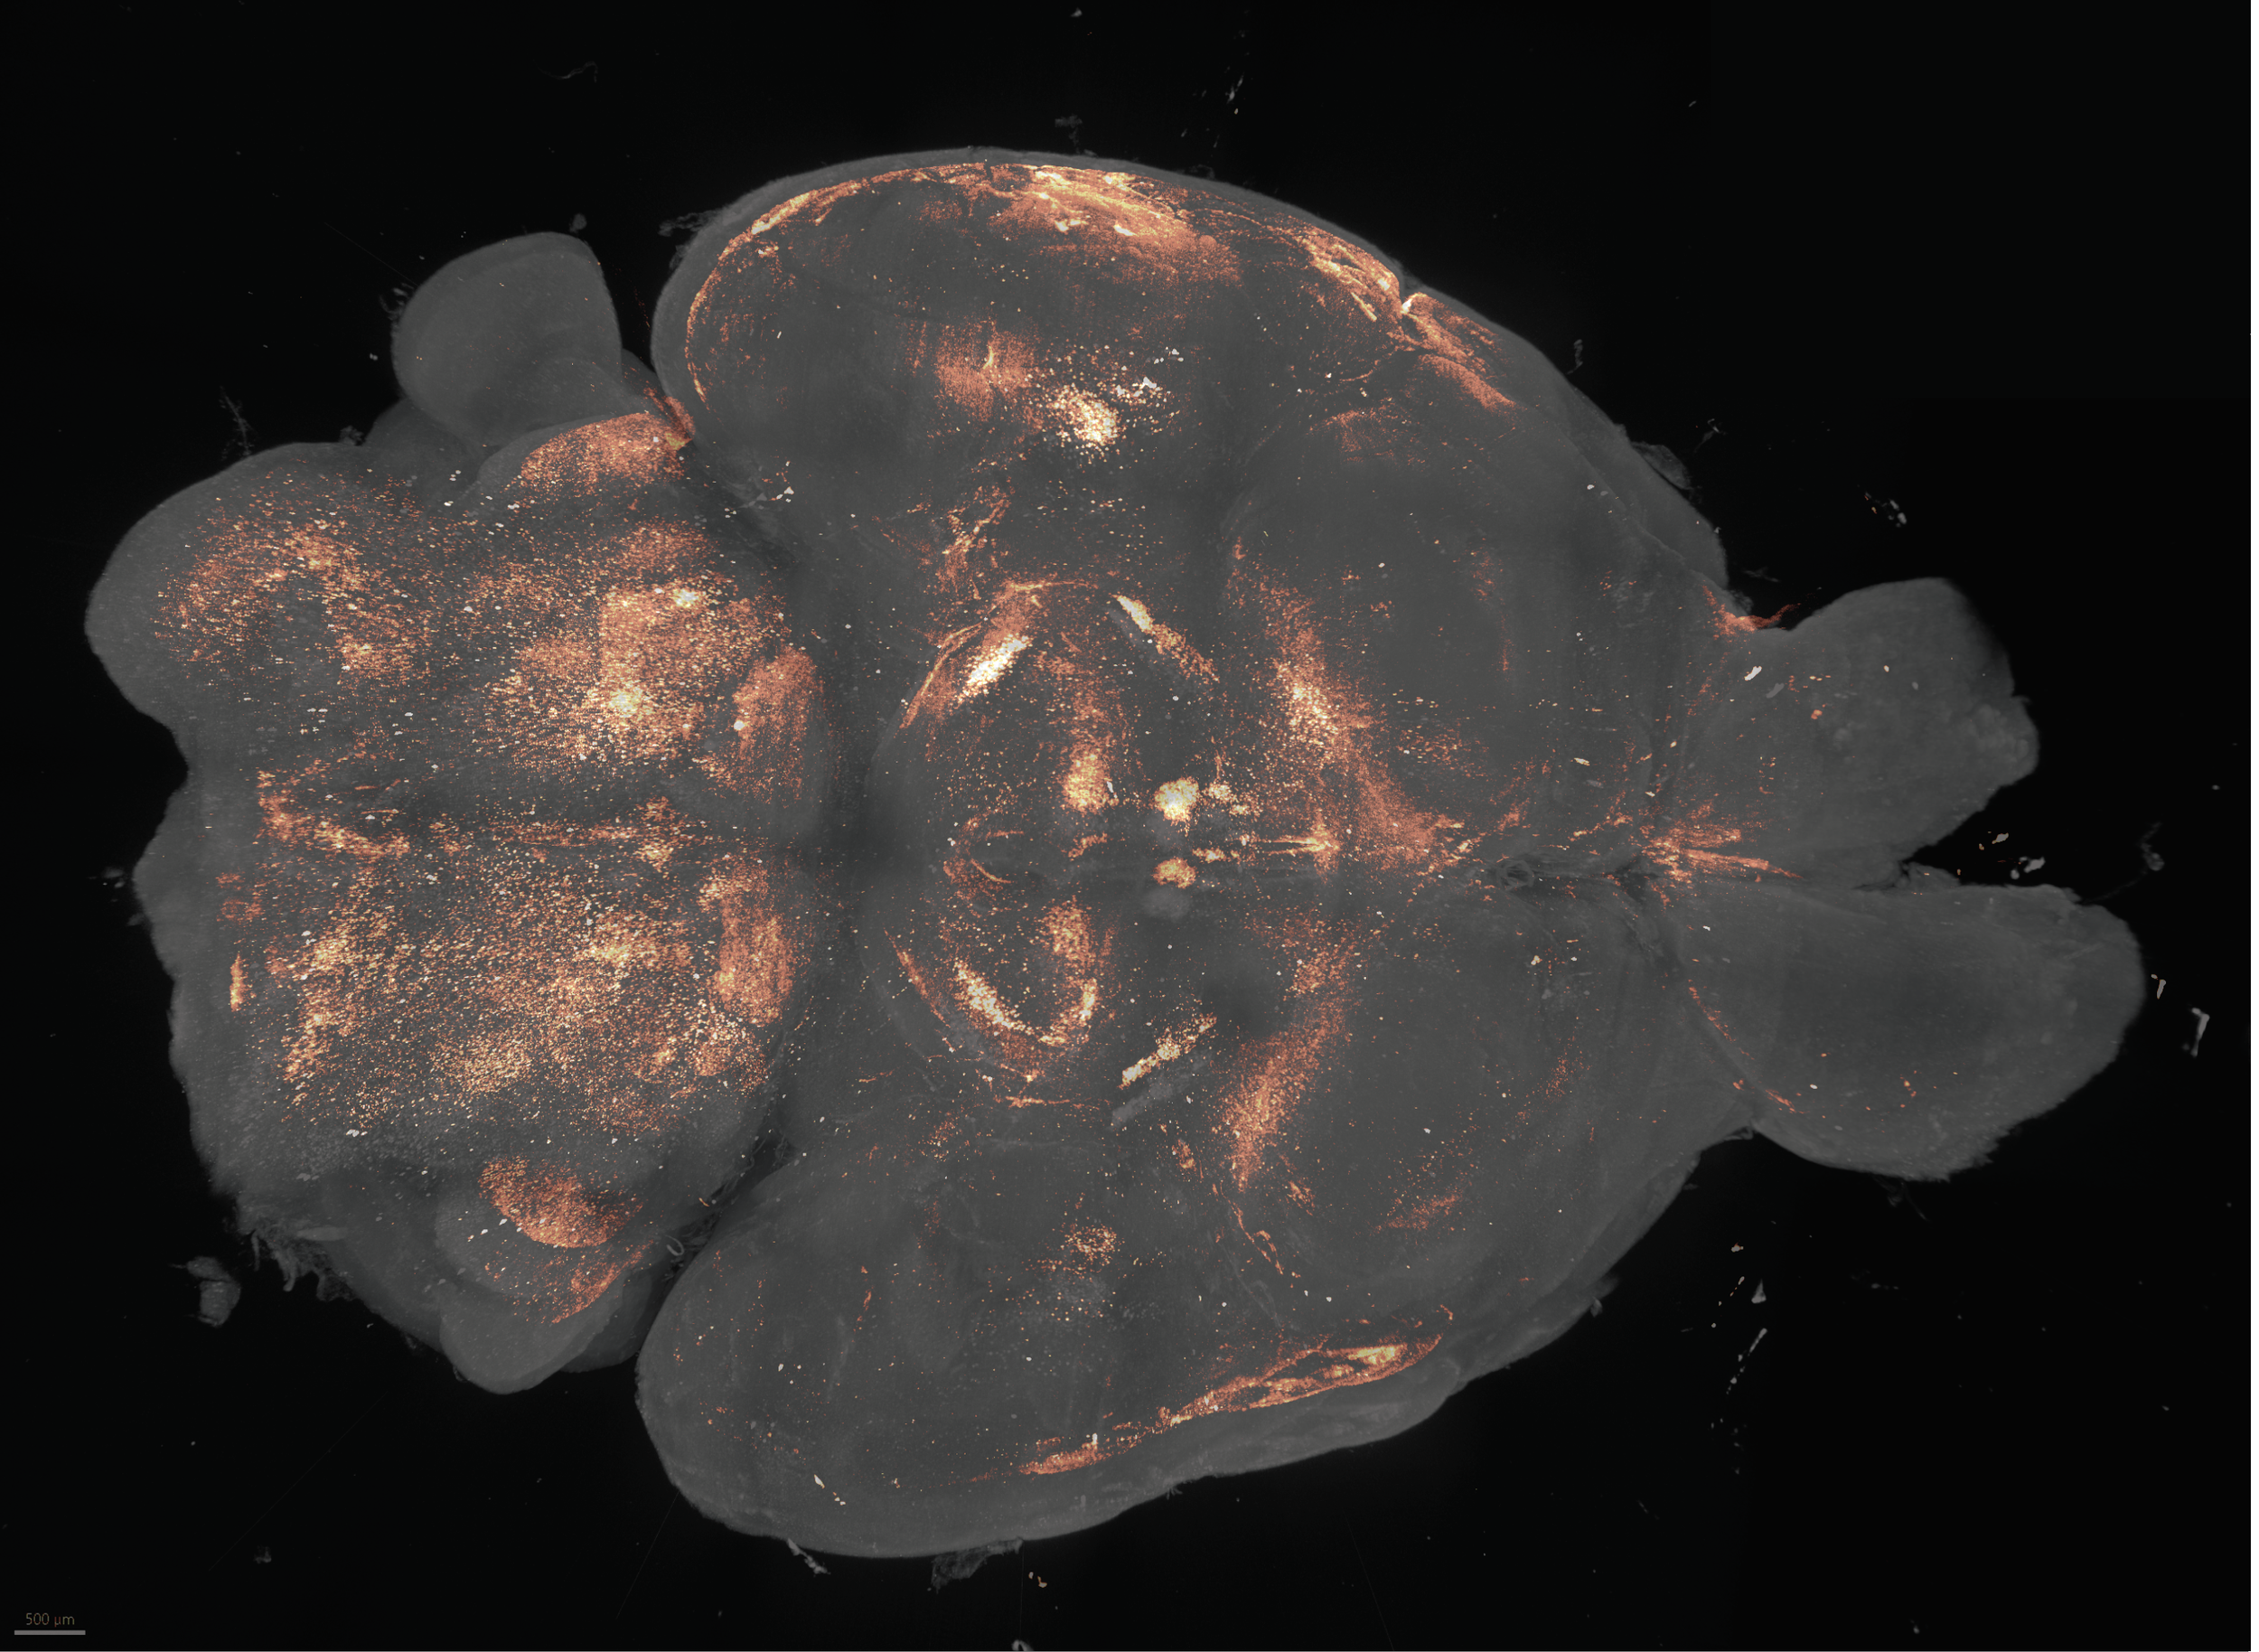

The brain coordinates all physiology. In aging these neural coordination hubs atrophy in surprising ways. We are finding out how these decaying circuits affect our physiology and new methods of targeting these brain regions to reverse aspects of aging.

(above: a whole brain lightsheet image showing neural coordination hubs in an aged mouse brain)